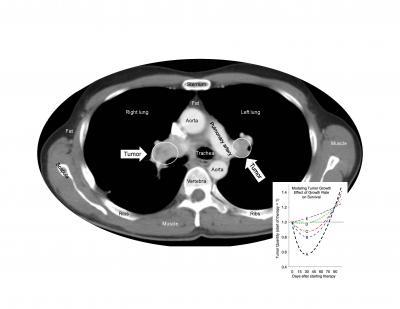

When Dr. Fojo and his colleagues analyzed more than 10,000 data points from the pivotal randomized phase 3 clinical trial that led to sunitinib's approval, the evidence clearly showed that no matter how long patients took sunitinib, it was not harmful, did not accelerate tumor growth, and did not shorten survival after treatment ended. During treatment, the drug slowed tumor growth and prolonged the patients' survival.

The researchers' findings indicate that sunitinib can benefit patients without altering tumor biology after the drug is stopped. "We hope this can be generalized to similar drugs but recognize that further studies will be needed," says first author Dr. Krastan Blagoev of the National Science Foundation. "Nevertheless, other drugs also approved worldwide for a variety of cancers—including sorafenib, pazopanib, and axitinib—are similar to sunitinib, and this will give some reassurances that one need not expect things to get worse after such drugs are discontinued."

(Photo Credit: Cell Reports, Blagoev et al.)